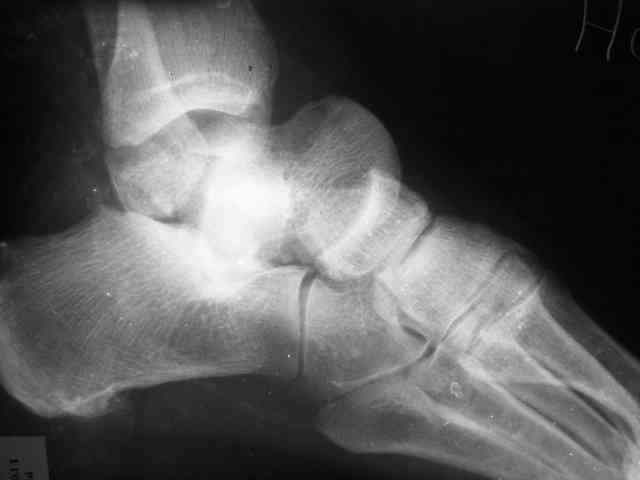

Уважаемый Александр! Как обещал представляю Р-граммы и операционные фото.

Ваши (лично ваши) рекомендации - астрагалэктомия-аппаратный пяточно-большеберцовый артродез с одновременным удлинением голени - правильно?

А удлинять голень в условиях плохих сосудов как? В смысле как потянутся склерозированные сосуды? Удлинять-то надо около 3 см.